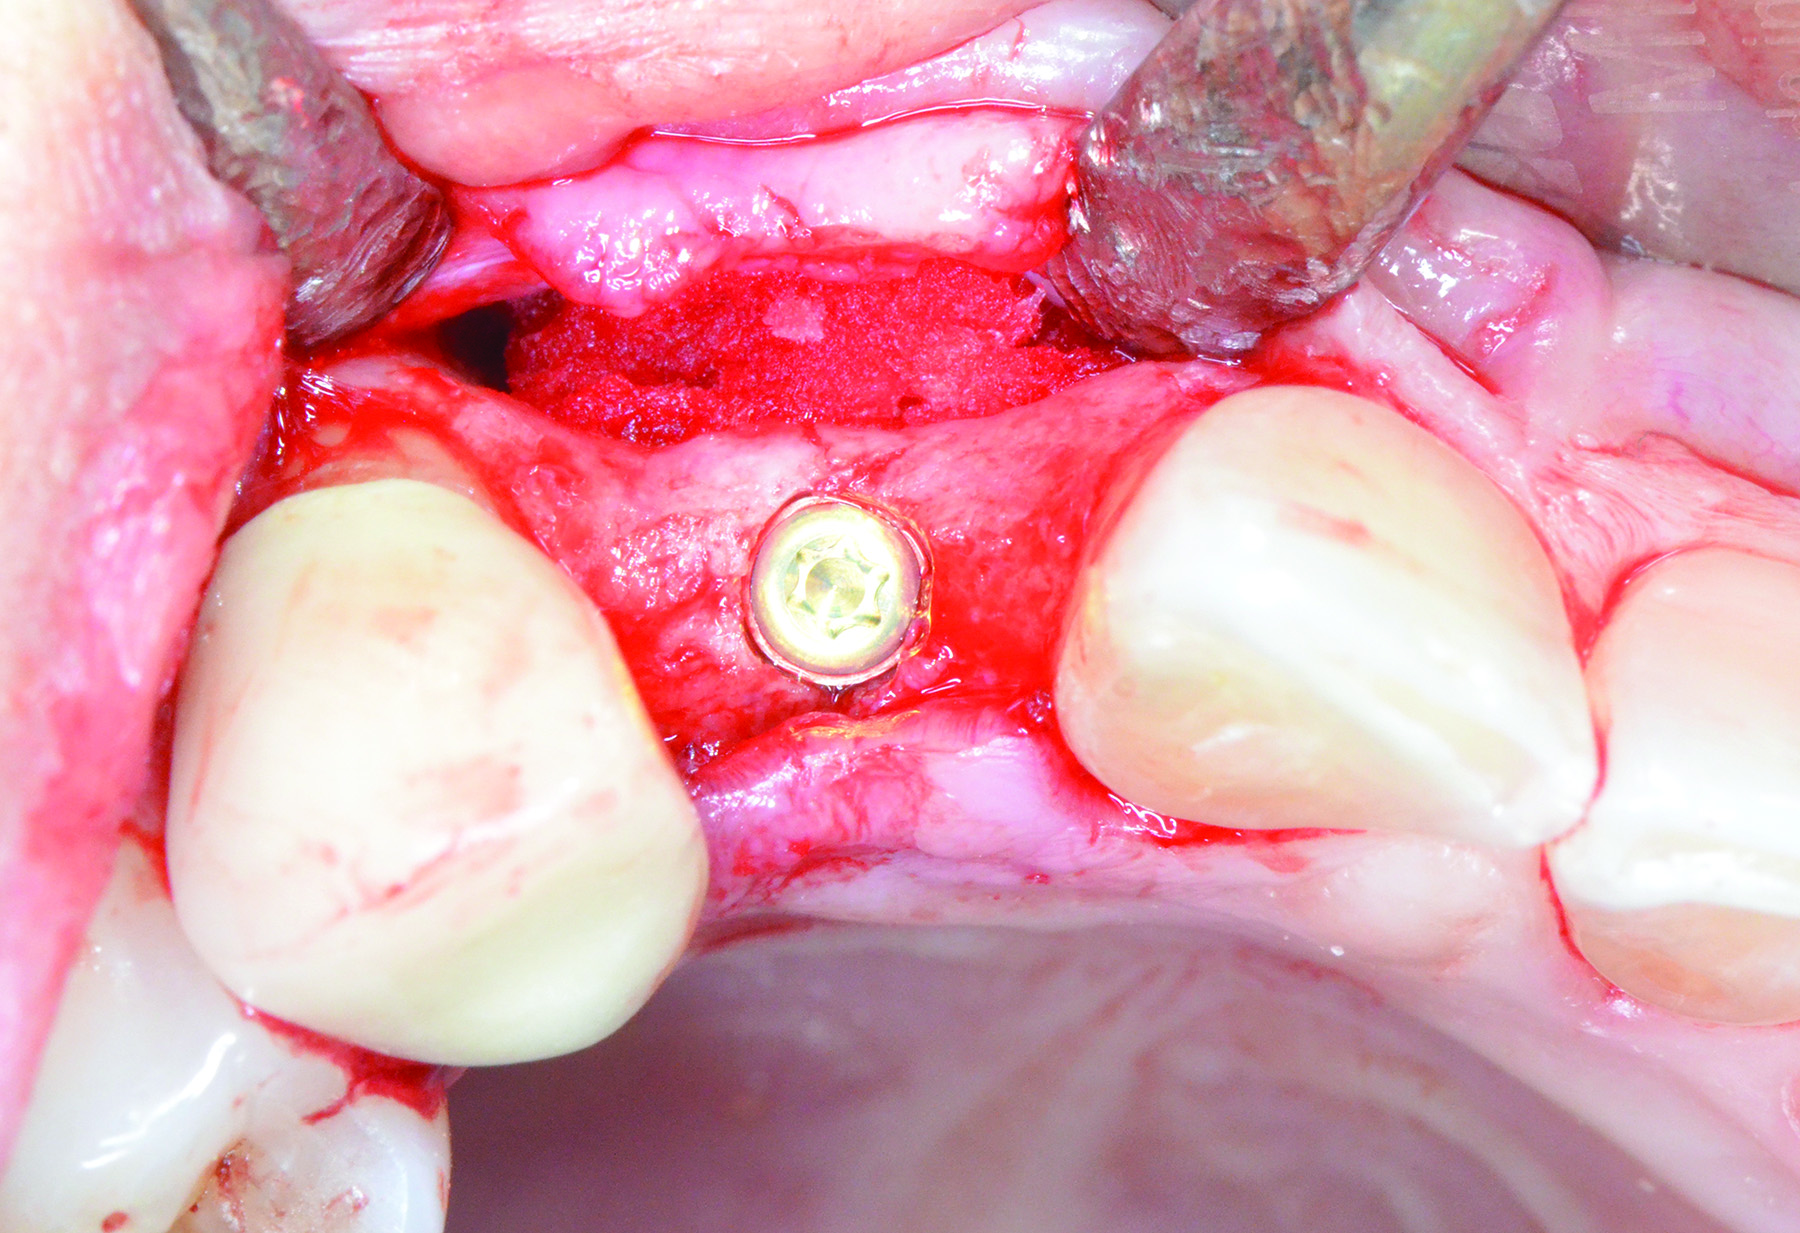

Fig 6 through Fig 8. Example of increasing KMW with an APF at implant uncovery. Fig 6: initial presentation showing lack of KMW; Fig 7: healing abutment placement with APF; Fig 8: 2 months post-treatment. (The dotted lines indicate the MGJ.) Fig 9 through Fig 11. Example of increasing KMW with an APF and FGG at implant uncovery.